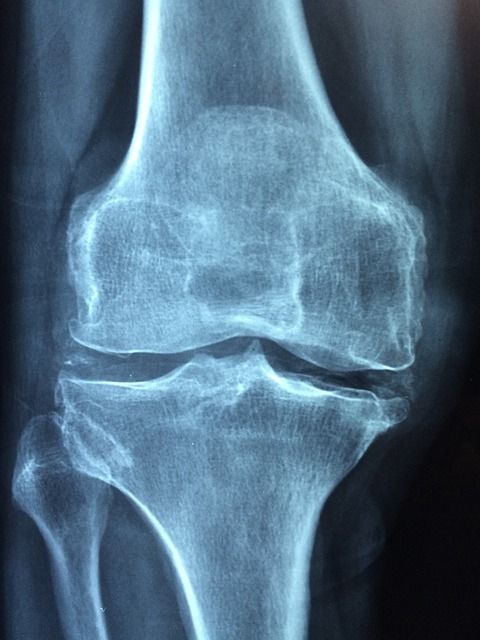

그 외에도 혈액 검사로 요산 농도를 측정하고, X선이나 초음파, CT 등의 영상 검사로 관절 손상과 통풍 결절을 확인할 수 있습니다. 급성 발작 시 혈중 요산 농도가 일시적으로 떨어질 수 있으니, 증상이 없을 때 검사를 반복하는 경우도 있습니다.

| 영상 검사 | X선, 초음파, CT로 관절 손상 및 결절 확인 |